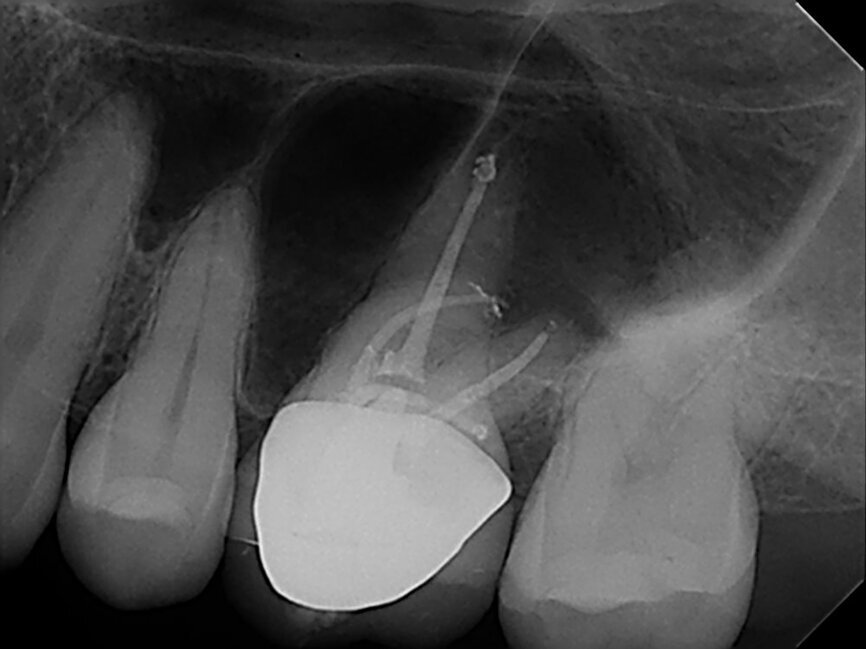

Before fitting the cones, I employed irrigation with ultrasonics using sodium hypochlorite, EDTA and chlorhexidine. I employed Gutta Percha Points and AH Plus sealer (Dentsply Sirona; Fig. 2).The radiograph to check cone fit revealed that a canal had been missed, so I captured a CBCT scan to locate the second mesiobuccal canal. The canal had an unusual buccal inclination to the palate, yielding the forked appearance of a snake’s tongue. I closed the cavity with calcium hydroxide and accessed the second mesiobuccal canal on the second visit.